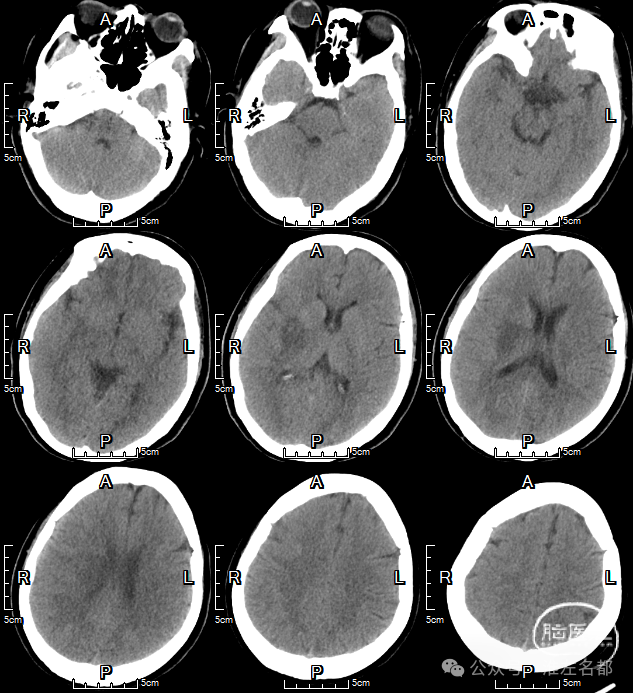

急诊多模式CT

CT平扫:ASPECT是9分,薄层MIP重建于右ICA末端至M2近端见长段血栓高密度影。

颅脑4D-CTA和颈部CTA示:右ICA末端至MCA M2近端长段闭塞,3型弓。

CTP:右MCA区大范围TTP显著延长,CBV和CBF仅在基底节区见小范围核心梗死征象。

术后第2日复查CT

CT平扫:右壳核低密度梗死。